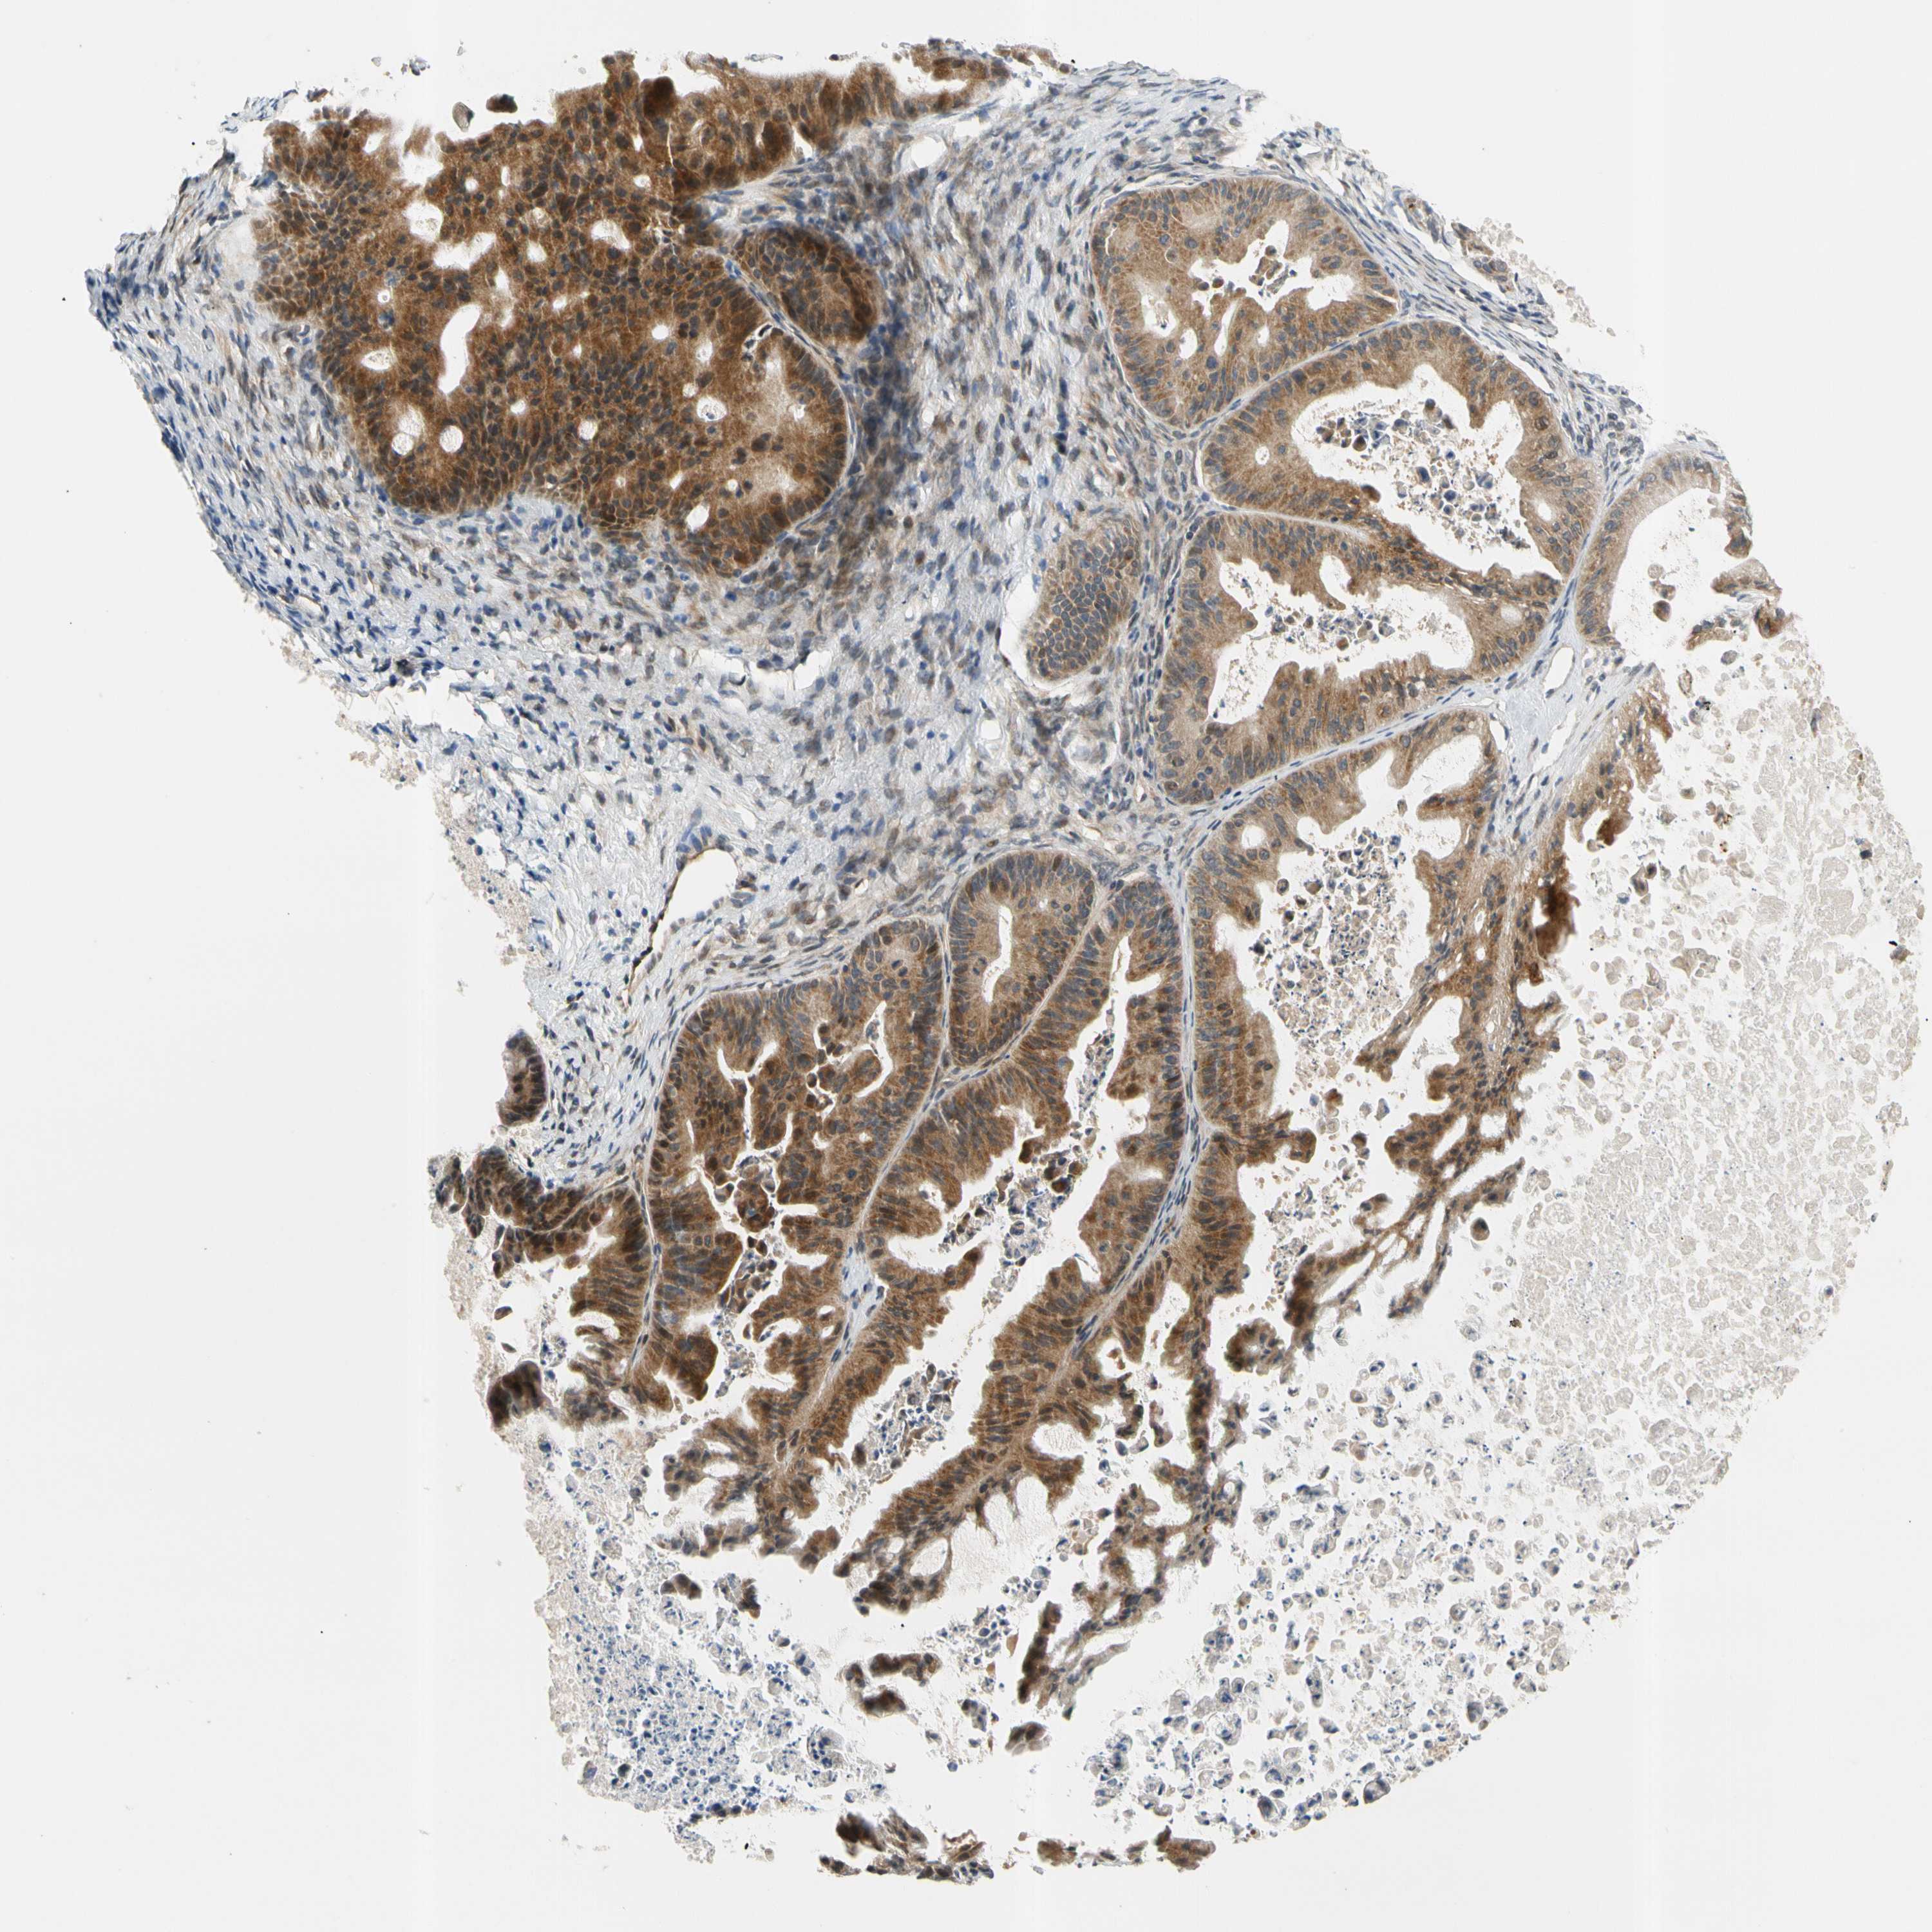

OVARIAN CANCER - Protein expressioni

A mouse-over function shows sample information and annotation data. Click on an image to view it in a full screen mode. Samples can be filtered based on level of antibody staining by selecting one or several of the following categories: high, medium, low and not detected. The assay and annotation is described here.

Note that samples used for immunohistochemistry by the Human Protein Atlas do not correspond to samples in the TCGA dataset.

Antibody stainingi

Antibody staining in the annotated cell types in the current human tissue is reported as not detected, low, medium, or high, based on conventional immunohistochemistry profiling in selected tissues. This score is based on the combination of the staining intensity and fraction of stained cells.

Each image is clickable and will lead to virtual microscopy that enables deeper exploration of all samples and also displays staining intensity scores, fraction scores and subcellular localization as well as patient and tissue information for each sample.

Antibody HPA008812

Staining

High

Medium

Low

Not detected

Intensity

Strong

Moderate

Weak

Negative

Quantity

>75%

75%-25%

<25%

None

Location

Nuclear

Cytoplasmic/membranous

Cytoplasmic/membranous,nuclear

Cystadenocarcinoma, serous, NOS

Carcinoma, endometroid

Cystadenocarcinoma, mucinous, NOS

Carcinoma, NOS